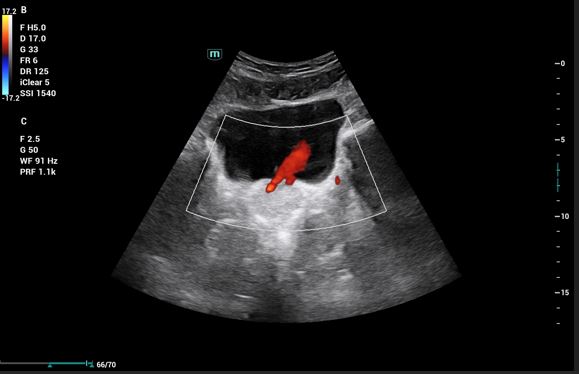

Pruebas complementarias: Sistemático de orina: microhematuria y ecografía abdominal: Riñones: (RD 11 cm, RI 12,09 cm), ecogenicidad, contornos y localización normales. RD: dilatación de la vía excretora Grado I dudosas imágenes de litiasis sin sombra acústica. No se evidencia líquido libre intrabdominal. Vejiga bien replecionada, jet ureteral bilateral simétrico, en trayecto del uréter derecho con Doppler color se observa artefacto de centelleo o efecto twinkling, que sugiere cálculo enclavado en unión vesicoureteral derecha.